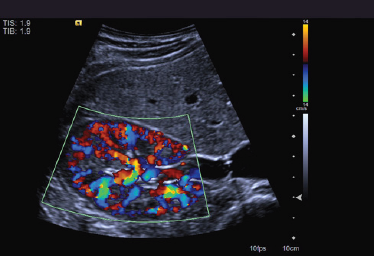

Elastografia

SIEMENS S2000 z zaawansowaną elastografią

Ultrasonograf uruchamia się bez żadnych problemów i wyświetlanych błędów. Klawiatura, trackball, przyciski wzmocnienia w bardzo dobrym stanie technicznym. Podnoszenie konsoli góra/dół, lewo/prawo działa prawidłowo. Wszystkie tryby obrazowania działają poprawnie. Ogólnie system i głowice w bardzo dobry stanie wizualnym i technicznym.